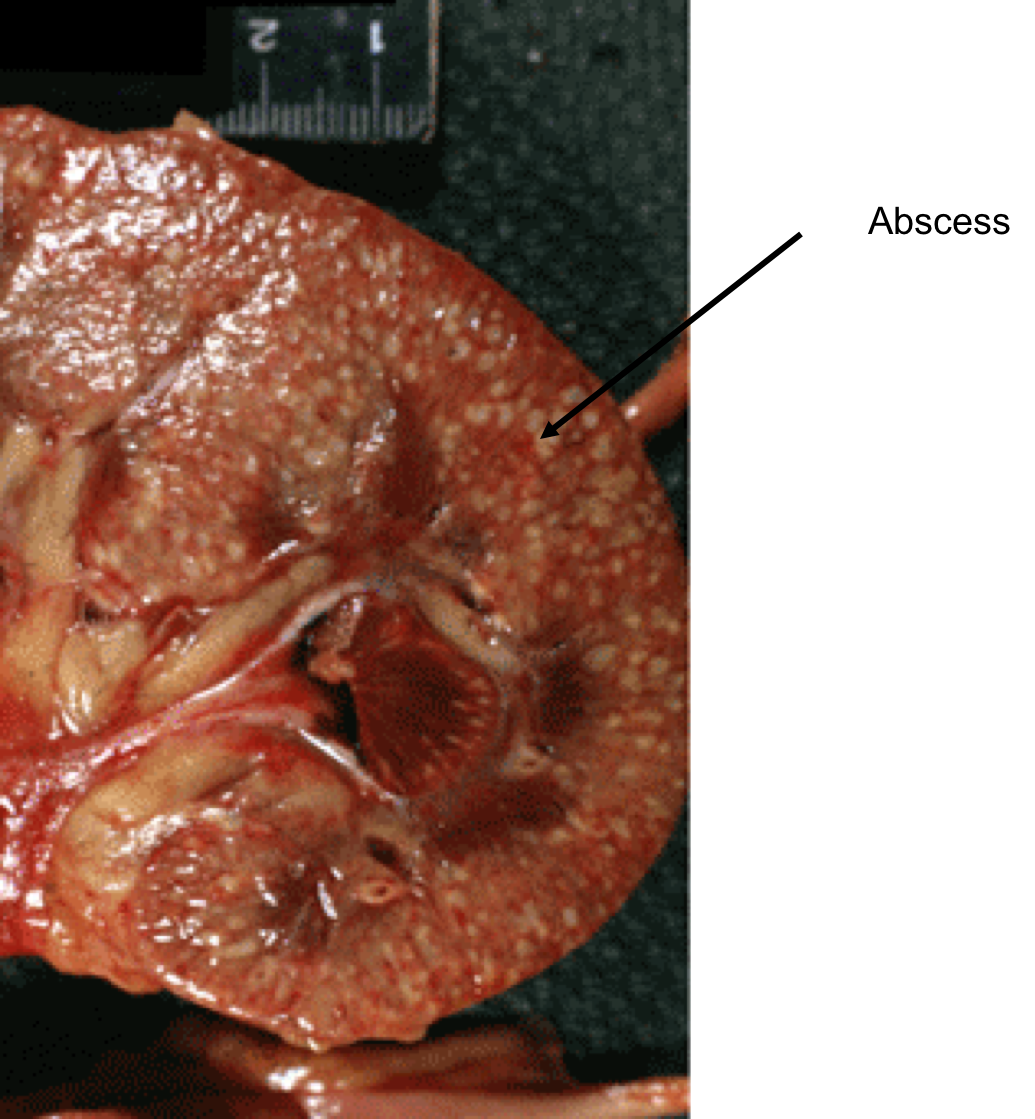

What is wrong with it? (this is one kidney cut in half and opened like a book, but we are seeing the capsular portion)

This is a fixed kidney demonstrating acute pyelonephritis